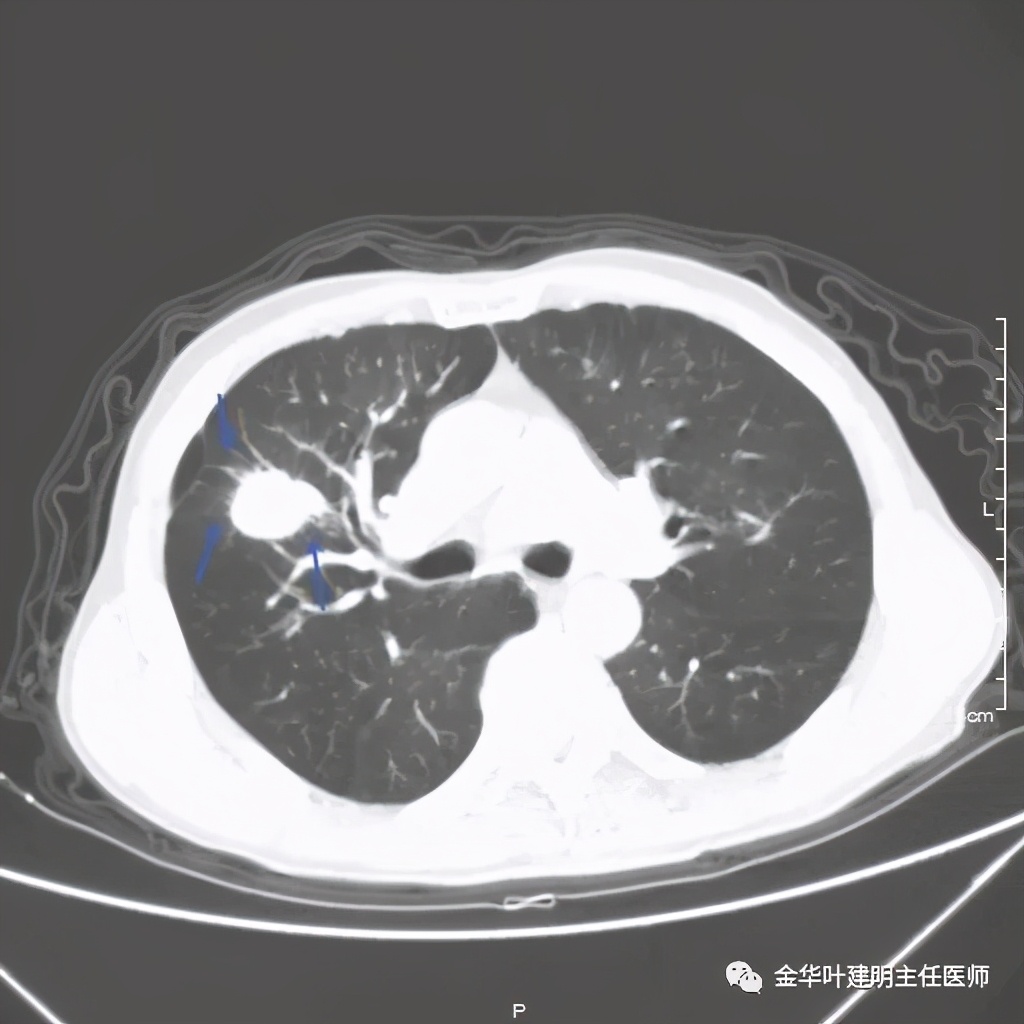

上图是穿刺时的某个层面,病灶的细毛刺征比较明显(蓝色箭头),病灶的边缘是不平的,而且有细短的毛刺样突向周围肺组织,这可是恶性的特征

桔色箭头示病灶周围血管征明显,有较粗的血管进入病灶,较细的也有

上图箭头示强化的血管与病灶关系密切,而且有被病灶侵犯影响的感觉,部分界限是不清楚的

上图示病灶内部有条索状的强化影,考虑是病灶内的新生血管可能性大

上图也见细毛刺,但不是特别广的范围,有的边缘还是相对比较光滑了点